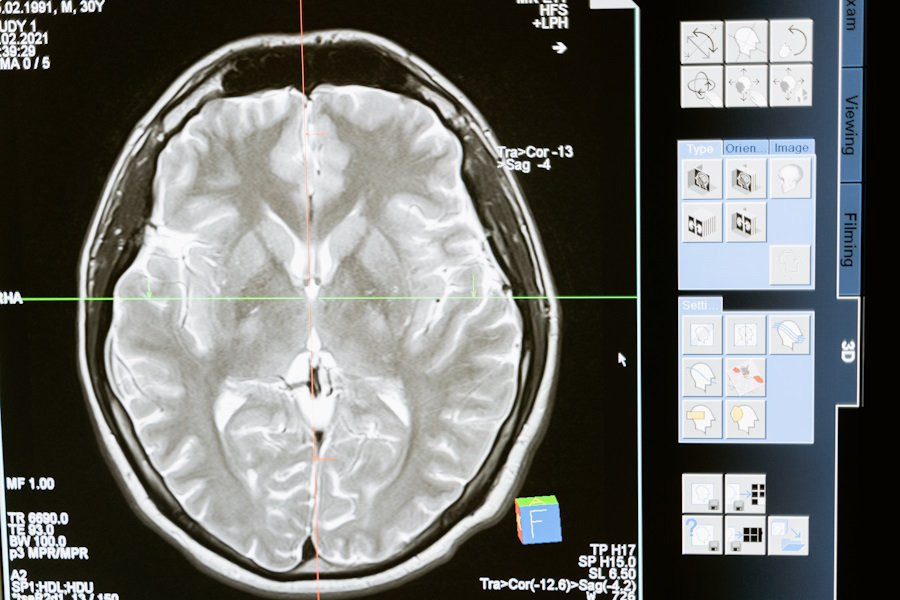

Научные открытия, сделанные исследователями Pitié-Salpêtrière Hospital (Париж, Франция) в области медицины, проливают свет на загадочное явление, известное как "волны смерти" в мозге. Это явление, возникающее при отсутствии кислорода в мозге, вызывает неожиданный всплеск активности, однако оно, вопреки своему названию, не является необратимым признаком смерти.

Согласно порталу Neurobiology of Disease, исследование, проведенное с использованием множества методов, включая многосайтовые внеклеточные локальные потенциалы поля и внутриклеточные записи от идентифицированных нейронов, обнаружило интересные аспекты этого феномена. Под руководством ученых была изучена активность коры мозга крыс при временной аноксии, или отсутствии кислорода.

Сразу после прекращения оксигенации мозга наблюдалась хорошо организованная последовательность стереотипных паттернов активности во всех слоях коры. Эта последовательность включала различные фазы активности, начиная с бета-гамма-активности и заканчивая электрическим молчанием.

Исследование также выявило, что нейроны в глубоких слоях коры были более активны и деполяризованы во время этой активации, в то время как поверхностные нейроны становились менее активными. Важно отметить, что распространение этого явления в мозге не происходило равномерно и имело сложный пространственно-временной профиль.

Ученые также обнаружили, что характер распространения "волн смерти" в мозге был связан с изменениями в регуляции клеточного метаболизма. Это открытие может иметь важные последствия для понимания механизмов, лежащих в основе необратимых повреждений мозга, связанных с кислородным голоданием.